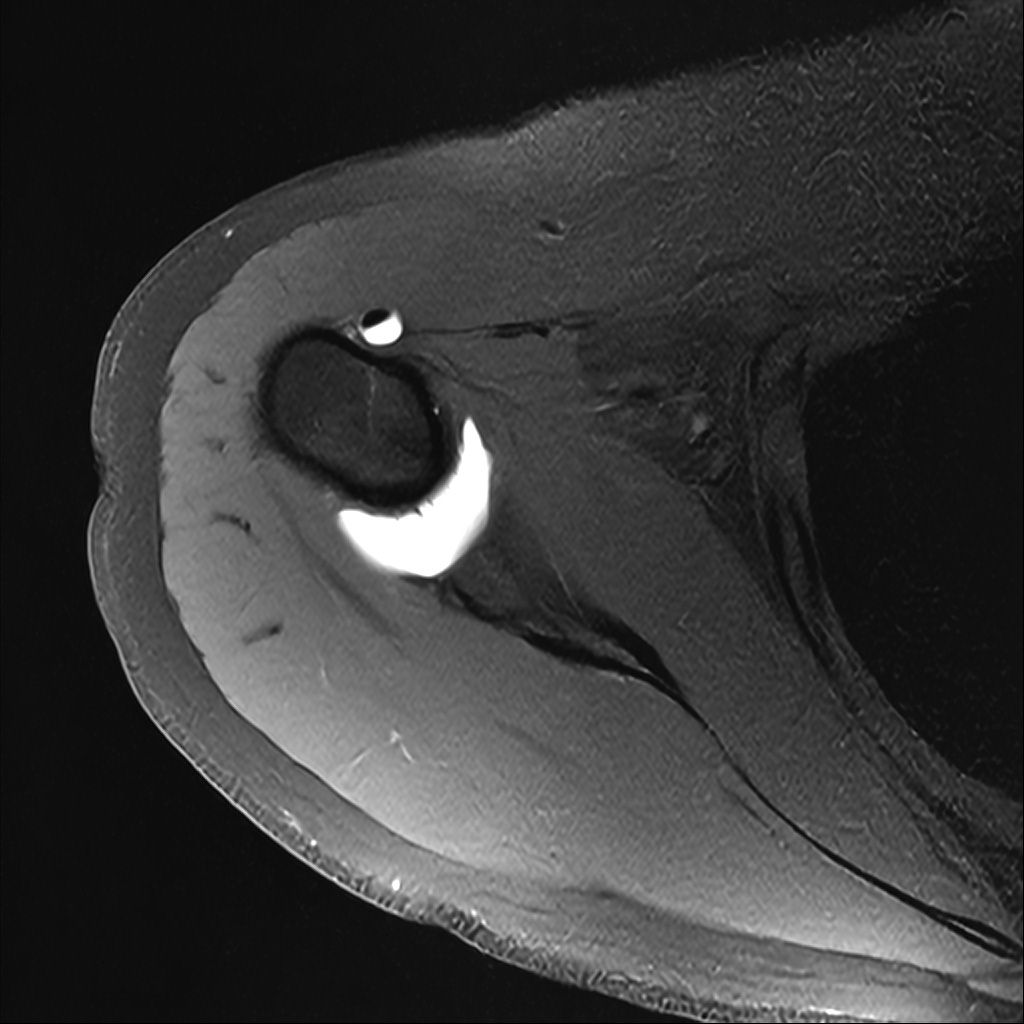

Mri 단면 영상으로 보아 어깨 관절 부위에서 이상 신호가 관찰되고 이는 관절 와순 파열의 가능성을 시사할 수 있습니다.

하지만 이영상만으로 정확한 진단은 불가능하고 정밀한 판단을 위해선 전체 시퀀스와 영상의학과 전문의의 공식판독이 필요합니다 특히 와순 파열은 위치와 동반 병변에 따라 해석이 달라집니다!